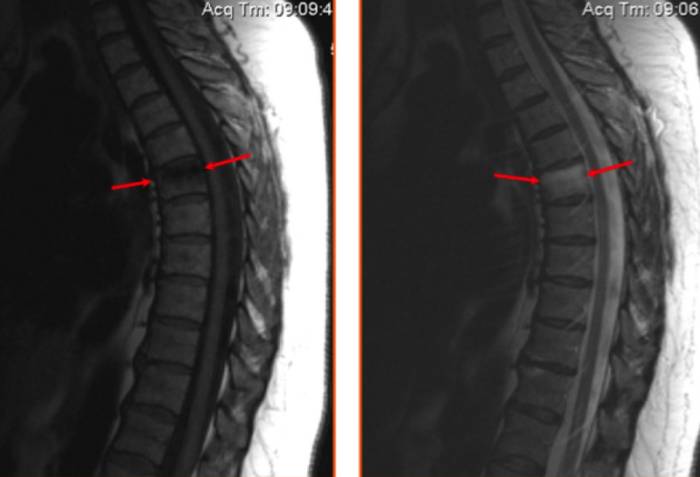

На МРТ изображении стрелками показан ушиб шестого грудного позвонка (визуализируется отек костных структур без деформации тела позвонка).